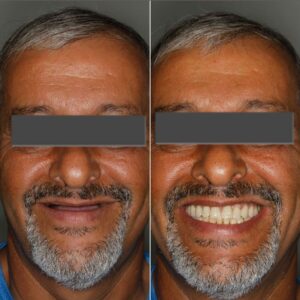

Ter dentes fixos e definitivos;

Deixar sua saúde bucal em dia;

Não fica caindo e soltando;

100% da mastigação de volta;

O implante dura para sempre;

É um tratamento simples;